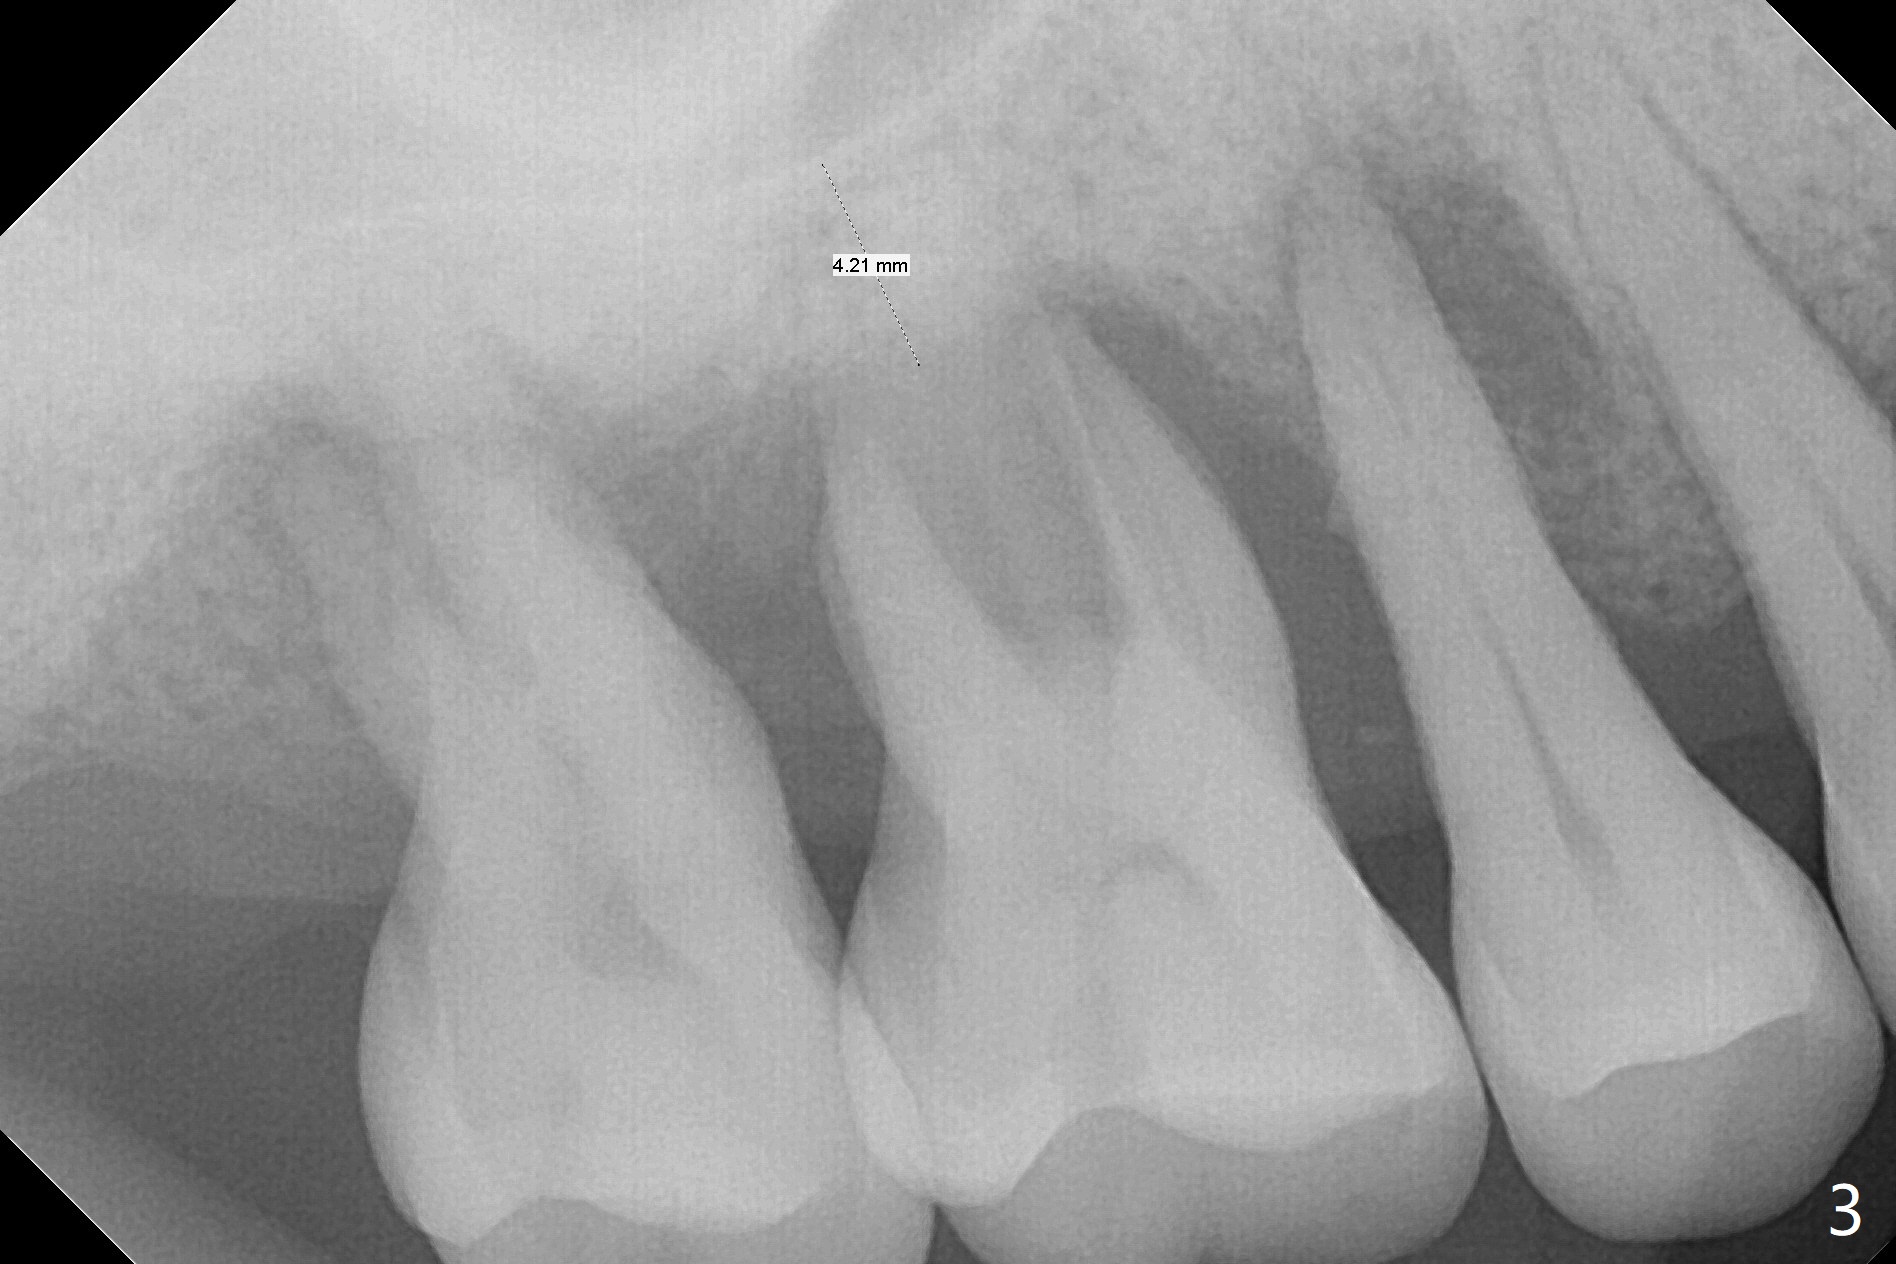

The tooth #3 has gingival recession moderate buccally (Fig.1) and severe palatally (Fig.2 P). The remaining bone height is estimated 4 mm (Fig.3). After extraction and debridement, the 3 sockets are packed with 2% Lidocaine 1:50,000 Epinephrine saturated gauze (Fig.4). When the gauze is removed from the buccal sockets (Fig.5 black area), the buccal portion (B) of the septal gingiva (*) is sectioned from the buccal gingiva (Fig.6 curved white line) and elevated from the underlying septal bone and pushed palatally (arrow). The septal gingiva (including the buccal portion) will be the palatal soft tissue wall of the subsequent osteotomy, providing blood supply to allograft to be placed. In short, the septum (through the buccal socket) will be the osteotomy site.

Initial osteotomy depth is 4 mm (Fig.7). The sinus membrane is found to be perforated when the depth increases to 8 mm. The latter could be prevented by taking CT and/or using osteotome. The subsequent osteotomy depth is 5 mm until 4.0 mm in diameter. When the 4.5 mm tap is inserted with initial stability, the shortest implant (8.5 mm, Fig.8 green) will be partially protruded into the sinus and partially exposed in the socket and the cuff of the abutment is expected to be around 6 mm (pink). Since the 5 mm tap achieves primary stability, a 5x8.5 mm implant (following placement of Osteogen plug to repair the perforated sinus membrane) is placed at the level just mentioned (Fig.9). Vanilla Graft mixed with minimal autogenous bone is packed (Fig.10.11 *) before and after insertion of a 6.5x5(4) mm abutment. An immediate provisional as well as a piece of Osteogen plug is fabricated to close the socket gap. The provisional and the abutment are dislodged 1 month postop (Fig.12). The wound has healed. The abutment is reloaded without the provisional. The implant appears to osteointegrate 4.5 months postop (Fig.13); in addition the bone graft seems to have migrated toward the roots of the neighboring teeth (arrows).